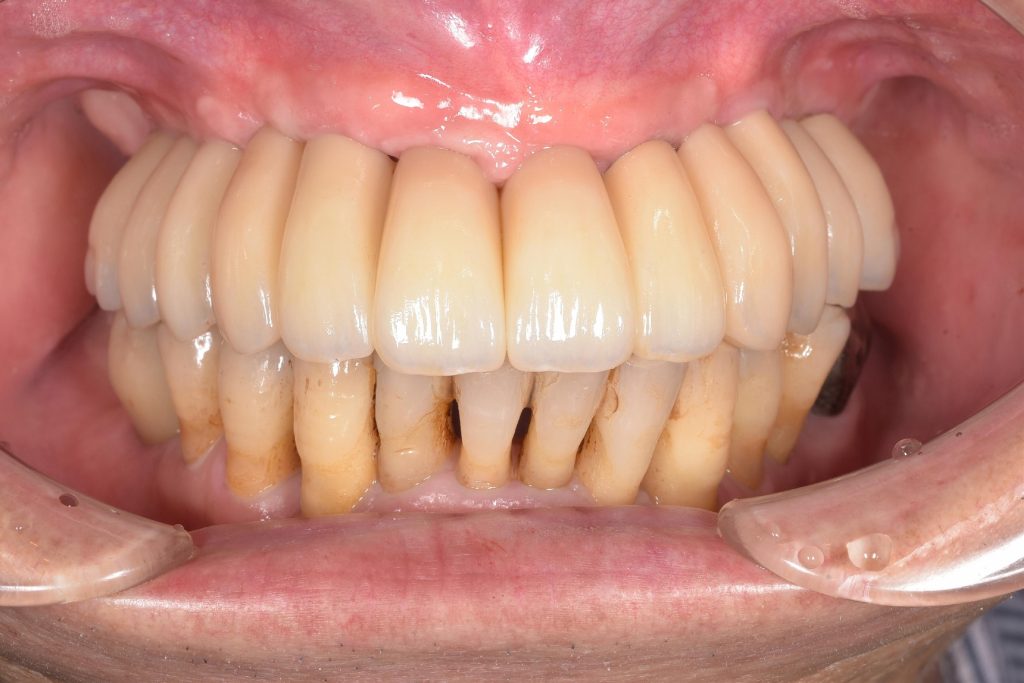

やはり、私が一番やりがいを感じるのは、患者様の笑顔であり、